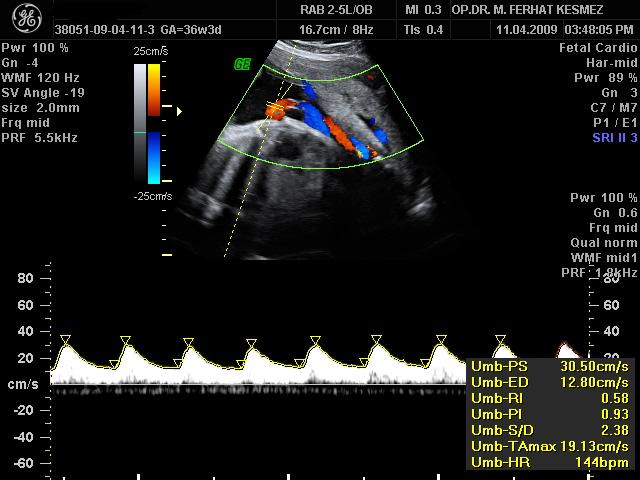

Ultrason Ölçümleri